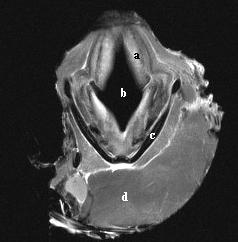

A study was performed to establish the appearance of normal equine laryngeal cartilages using magnetic resonance imaging. Specimens were acquired from clinically normal horses that were euthanized for reasons other than respiratory disease. Three in situ and 5 ex vivo larynges were imaged using a 0.3 Tesla system. Images were obtained in the transverse plane using T1-weighted 3D spin echo, T2-weighted 3D spin echo, T2-weighted gradient echo, short tau inversion recovery (STIR), and proton density spin echo sequences. Five ex vivo larynges were also imaged in the transverse plane using a 1.5 Tesla system, sequences included T1-weighted 3D spin echo, T2-weighted 3D turbo-spin echo, turbo inversion recovery (TIRM), and proton density spin echo sequences. A frozen gross laryngeal specimen was sliced in 5-mm transverse sections for comparison to the MR images. Excellent correlation was found between MR images and the gross transverse sections. Successful imaging was accomplished using both imaging systems; however, the 1.5 Tesla system yielded superior image resolution. The 0.3 Tesla imaging system would accommodate the intact equine head, which was not possible using the 1.5 Tesla MRI system. The internal morphology of the laryngeal cartilages was clearly identified in all imaging sequences obtained. Cartilages were found to differ in signal intensity based on the tissue composition and imaging sequences performed. MRI was determined to be a useful imaging modality for evaluating the cartilage morphology of the equine larynx. Further investigation is required to document pathologic morphology.